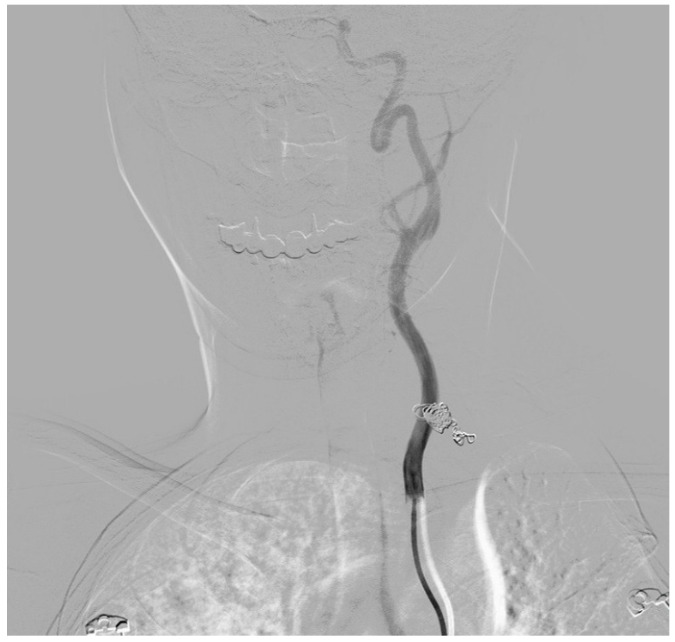

Case presentation: We present the case of a 33-year-old woman in the puerperium with neurofibromatosis type 1 who had a vertebral symptomatic artery aneurysm. During a previous hospitalization, two months before the treatment of the vertebral aneurysm, a same-sided aneurysm of the thyrocervical trunk was successfully treated with endovascular coiling because of aneurysm rupture. In this case report, the vertebral artery aneurysm was successfully managed using a flow diverter stent graft.

Conclusions: This is the first reported case of a successfully treated symptomatic vertebral artery aneurysm with a flow diverter stent graft in a patient with neurofibromatosis type 1 during the early puerperium. Endovascular treatment with a stent graft is a minimally invasive, safe, and effective treatment for patients with vertebral artery aneurysms. Early diagnosis of non-ruptured vertebral artery aneurysms is a crucial as well as appropriate treatment, which should be undertaken in a timely manner to prevent serious complications or a fatal outcome.